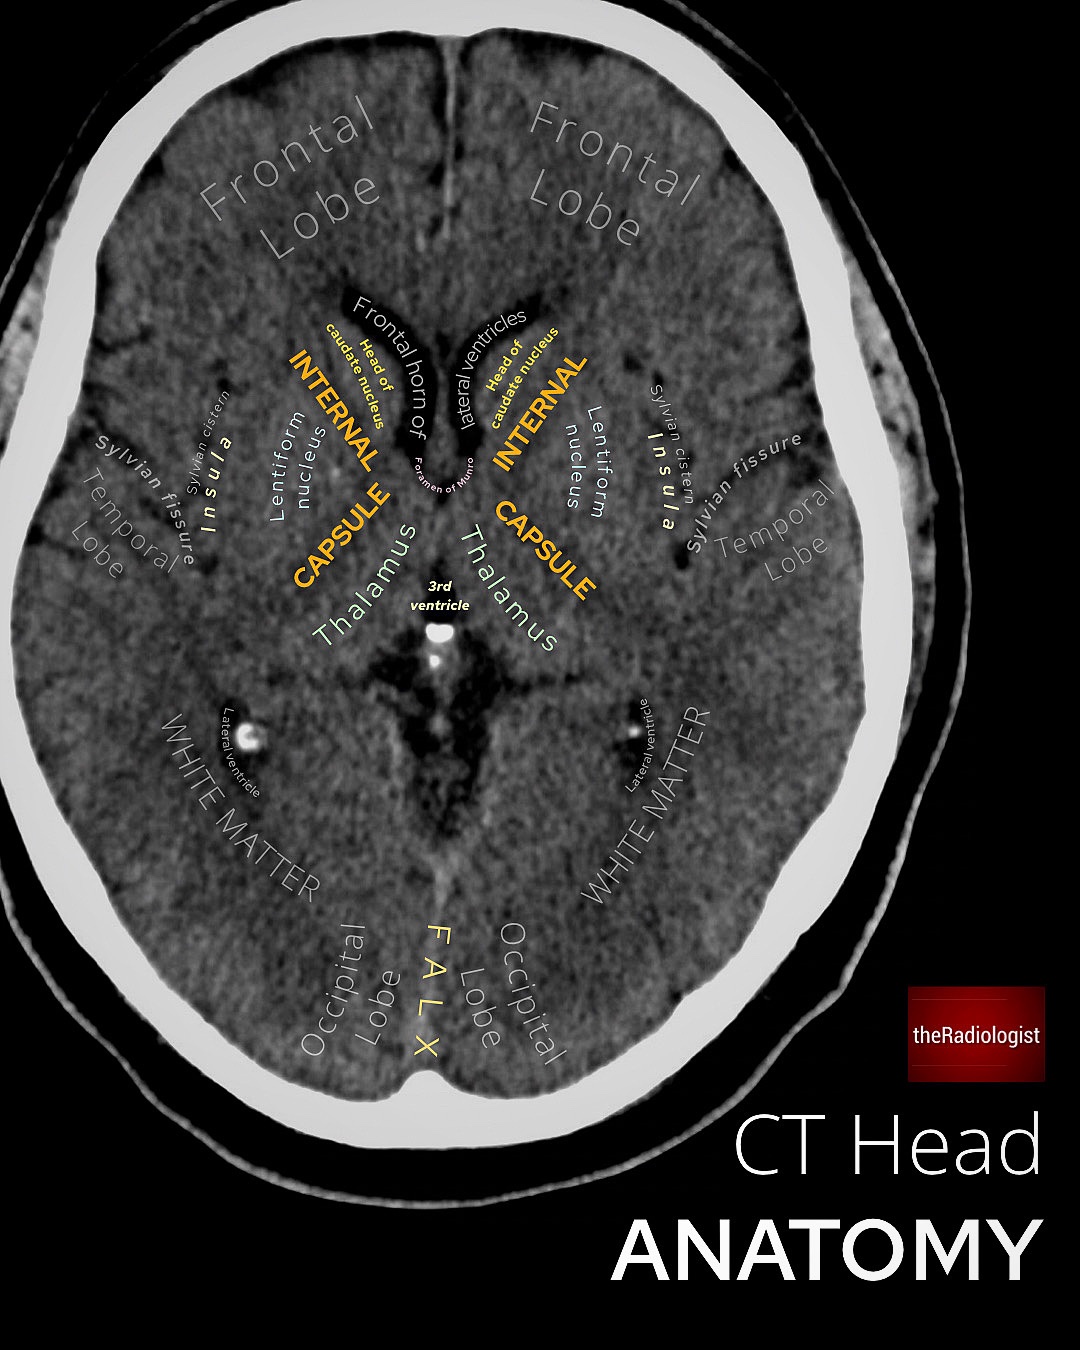

Basal Ganglia Function and Location